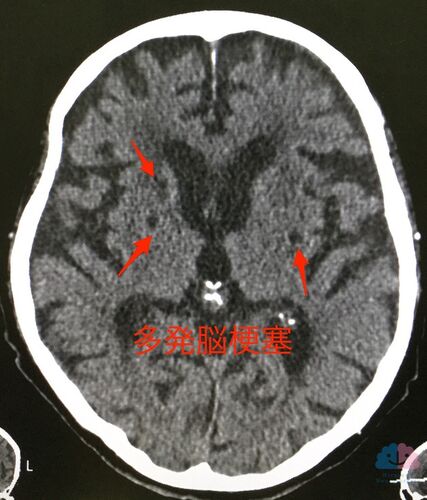

【症例報告】突然せん妄を起こした90代の男性に行った治療。

1ヶ月前のある日の夜から突然、おかしなことを言いながら毎晩家の中を膝行って徘徊するようになった90代の男性MTさん。 頭部CTを行ったところ、脳梗塞痕を多数認めた。